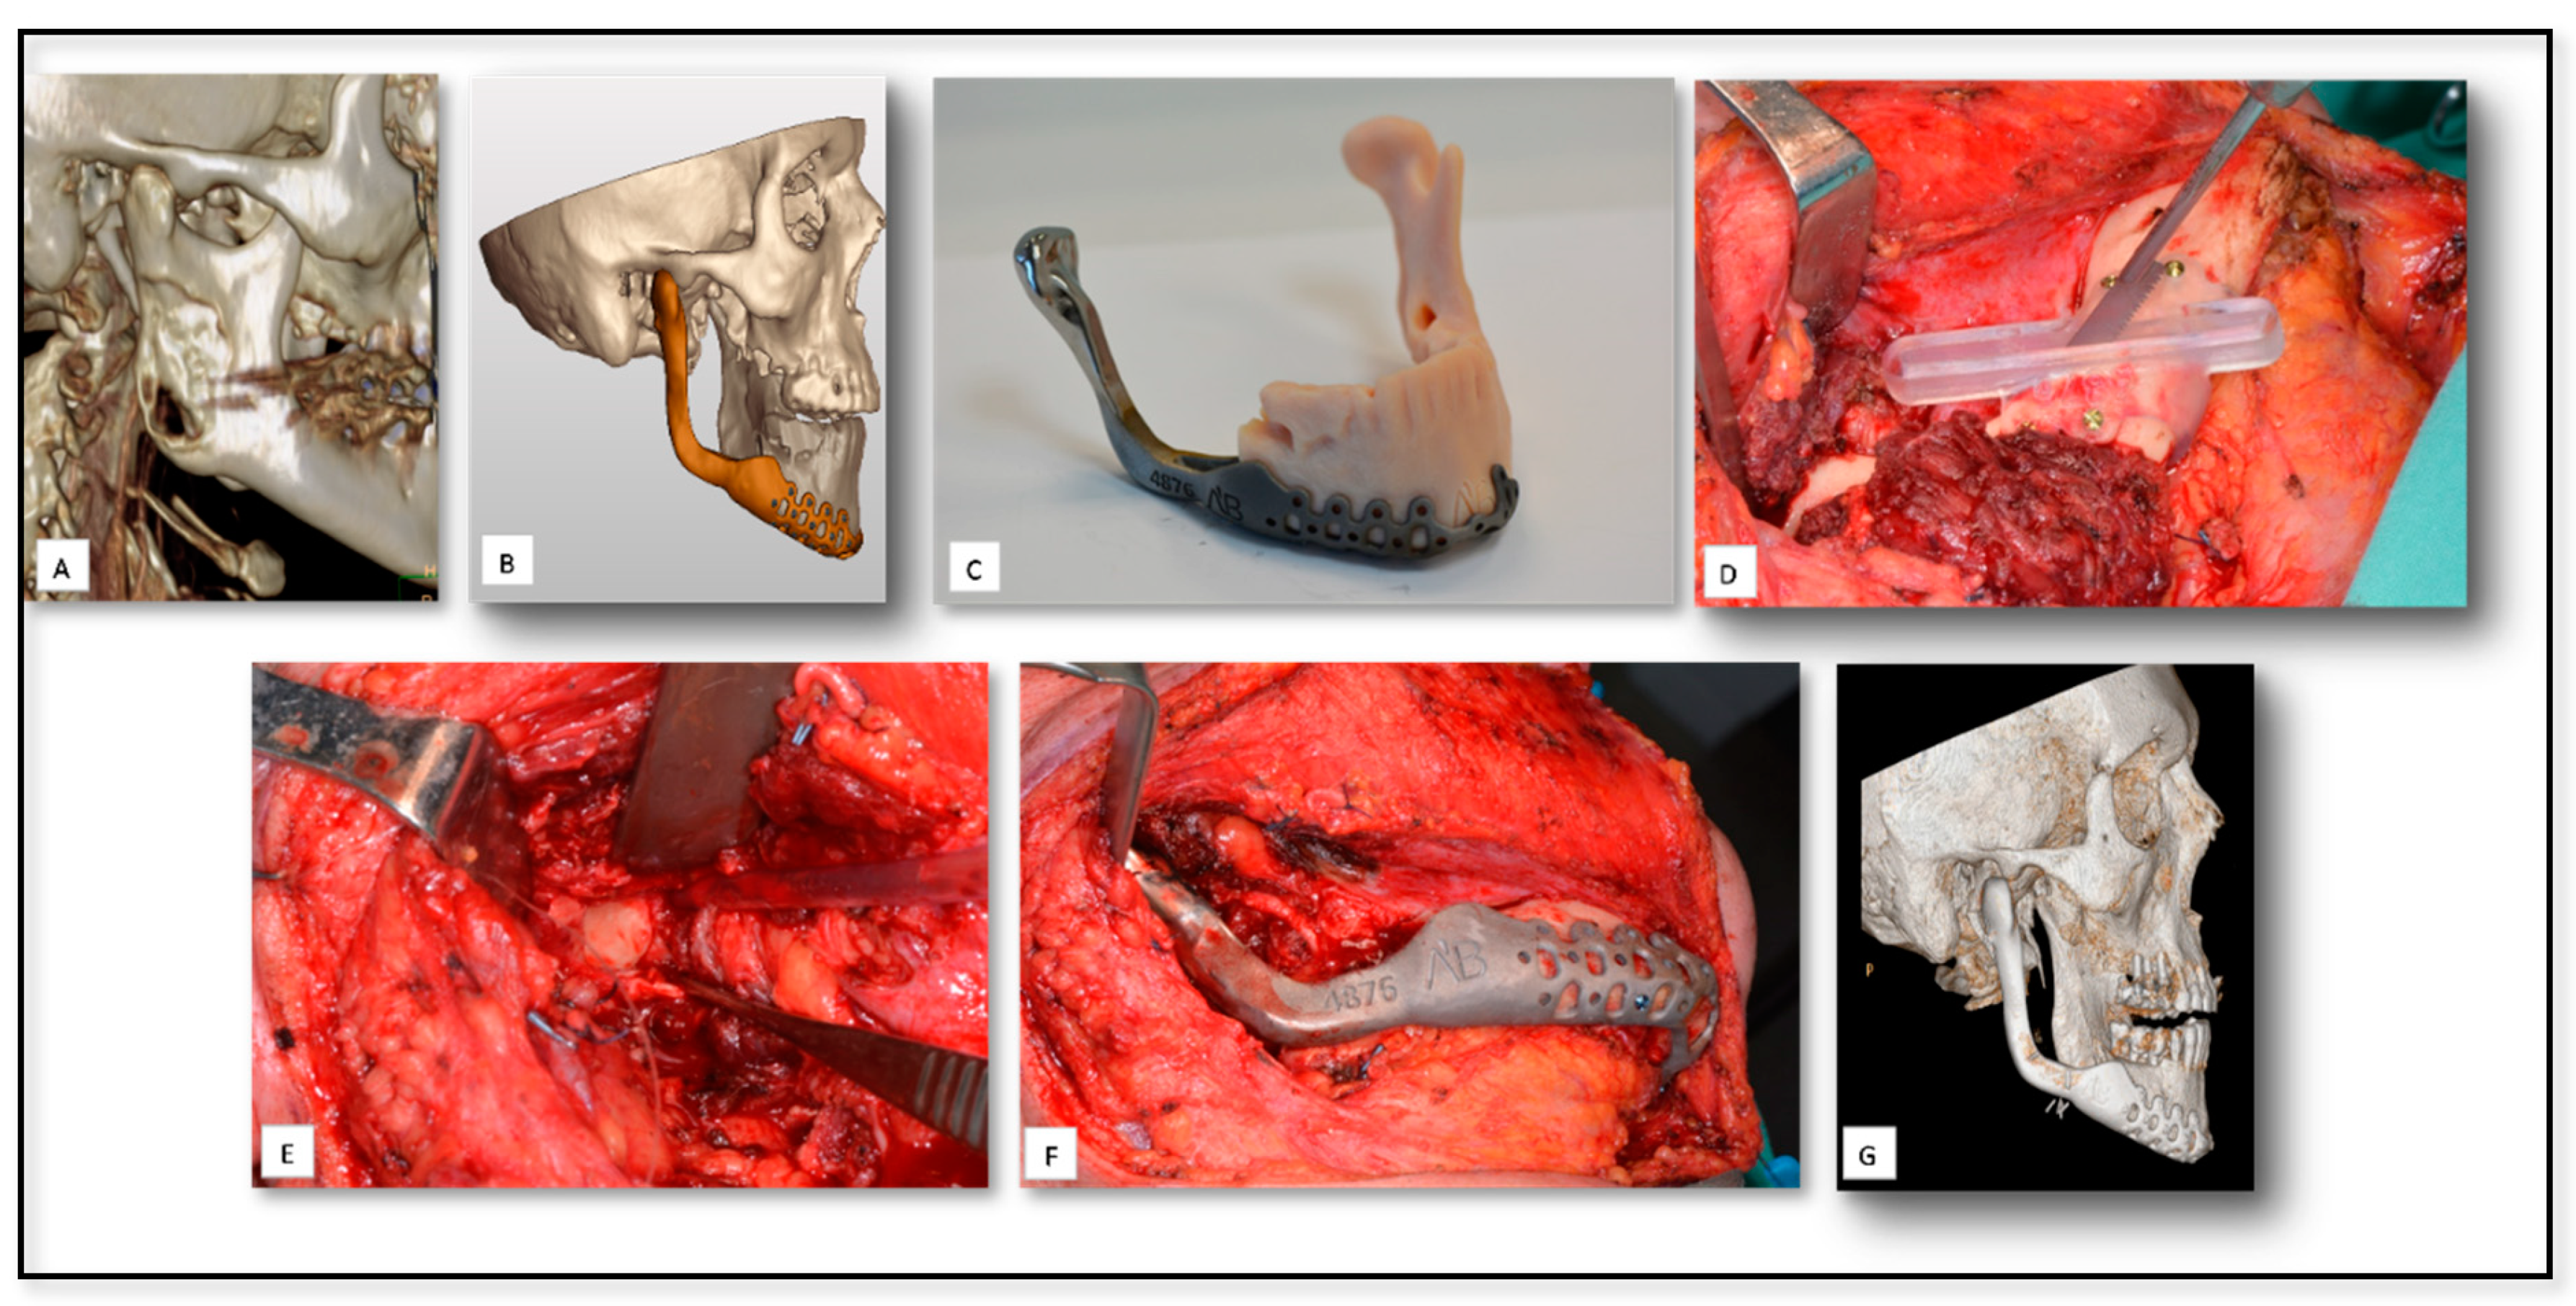

5.4. AM for Temporomandibular Joint (TMJ) Reconstruction Surgery Due to Oncologic Rresection

5.5. AM for Producing PSI for Reconstruction of Large Mandibular Defect after Tumor Resection